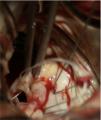

Figure 4.

Intraoperative view showing the forceps holding the detached muscle head. The two primary cords connecting the muscle head to the edge of the posterior leaflet are clearly seen.